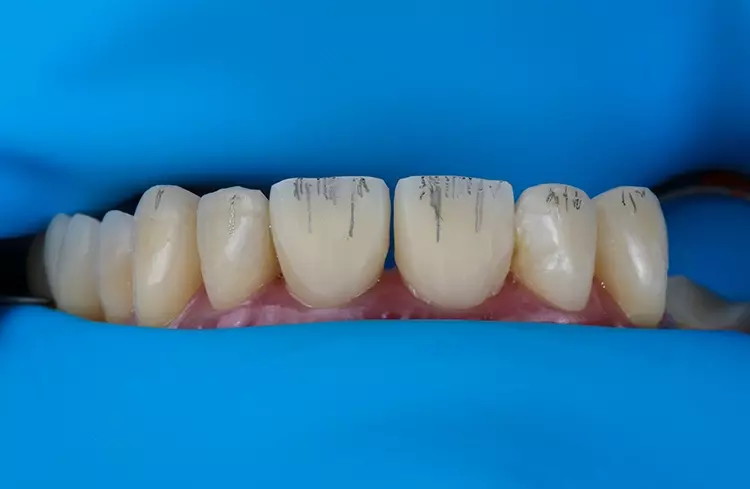

Die Kronen für 11 und 21 wurden mit einer 5-Achs-Fräs- und Schleifmaschine (inLab MC X5; Dentsply Sirona) aus einer nanokeramischen Komposit CAD/CAM-Ronde (Grandio disc, A1, VOCO) gefräst und mit Bifix Hybrid Abutment (VOCO) auf einem Abutment aus Metall (Grand Morse, Neodent Titanium Base Neodent, Straumann) im Labor zementiert. Die Kronen wurden in ihrer endgültigen Position eingegliedert (Abb. 18). Jede Krone wurde mit direkten Komposit-Veneers modifiziert.

Das Ergebnis entsprach den Erwartungen des Patienten. In der Nachbehandlungsphase wurde die Okklusion erfolgreich wiederhergestellt, wobei eine neue vertikale Dimension, eine passende Kronenform und -größe sowie funktionsorientierte Okklusionsebenen erreicht wurden.

Es konnten sofortige positive ästhetische und funktionelle Verbesserungen beobachtet werden, die auch 6 Monate nach Eingliederung noch deutlich sichtbar sind. Darüber hinaus wurden okklusale Stabilität und korrekte Zahnführungen erreicht.